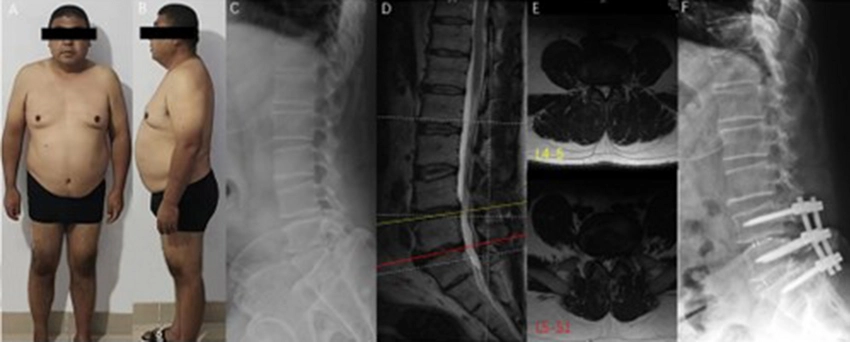

An overview of what is spinal stenosis